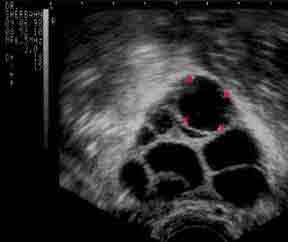

after a week of looking at ulatrsounds that resemble this:

(Those black spots are follicles/eggs growing in the ovary) I had about 15 eggs, 4-6 of which will be ready to be released at ovulation. Today, I do feel like my ovaries may burst. they are huge. I can barely stand up. It’s crazy how much those gals can grow!)